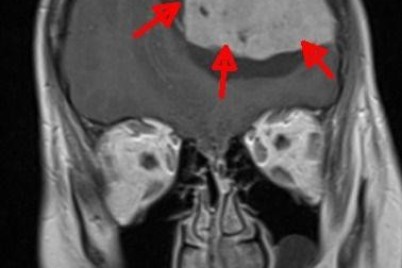

الرياض - هدى الخطيب نجح فريق جراحة المخ والأعصاب في مستشفى الملك سلمان من استئصال ورم في الدماغ لسيدة ثلاثينية...